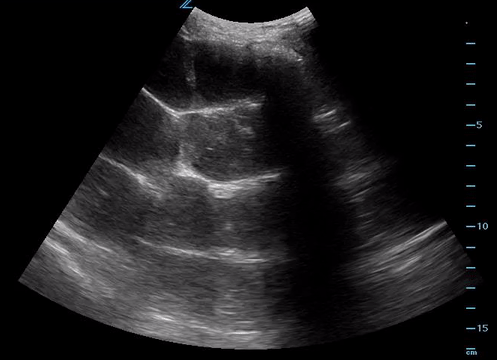

To-and-fro or pendulous peristalsis

As well as hyperechoic spot echos (feculent matter)